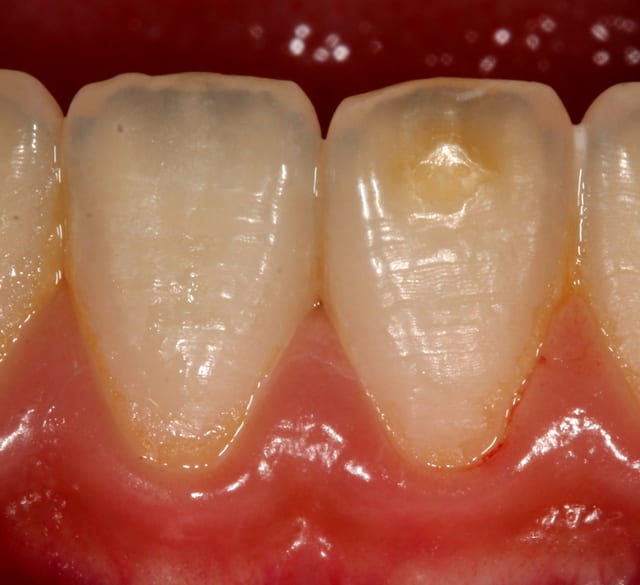

Un trauma, notamment une impaction, peut perturber les germes et on observe alors des hypoplasies typiques (photo ci-dessous). Dans le cas dont tu parles, les infections ne font-elles pas suite à un trauma ? As-tu des photos à nous montrer ?

Je parle d'un émail d'aspect brun, friable et fragile, plus sensible à la carie.